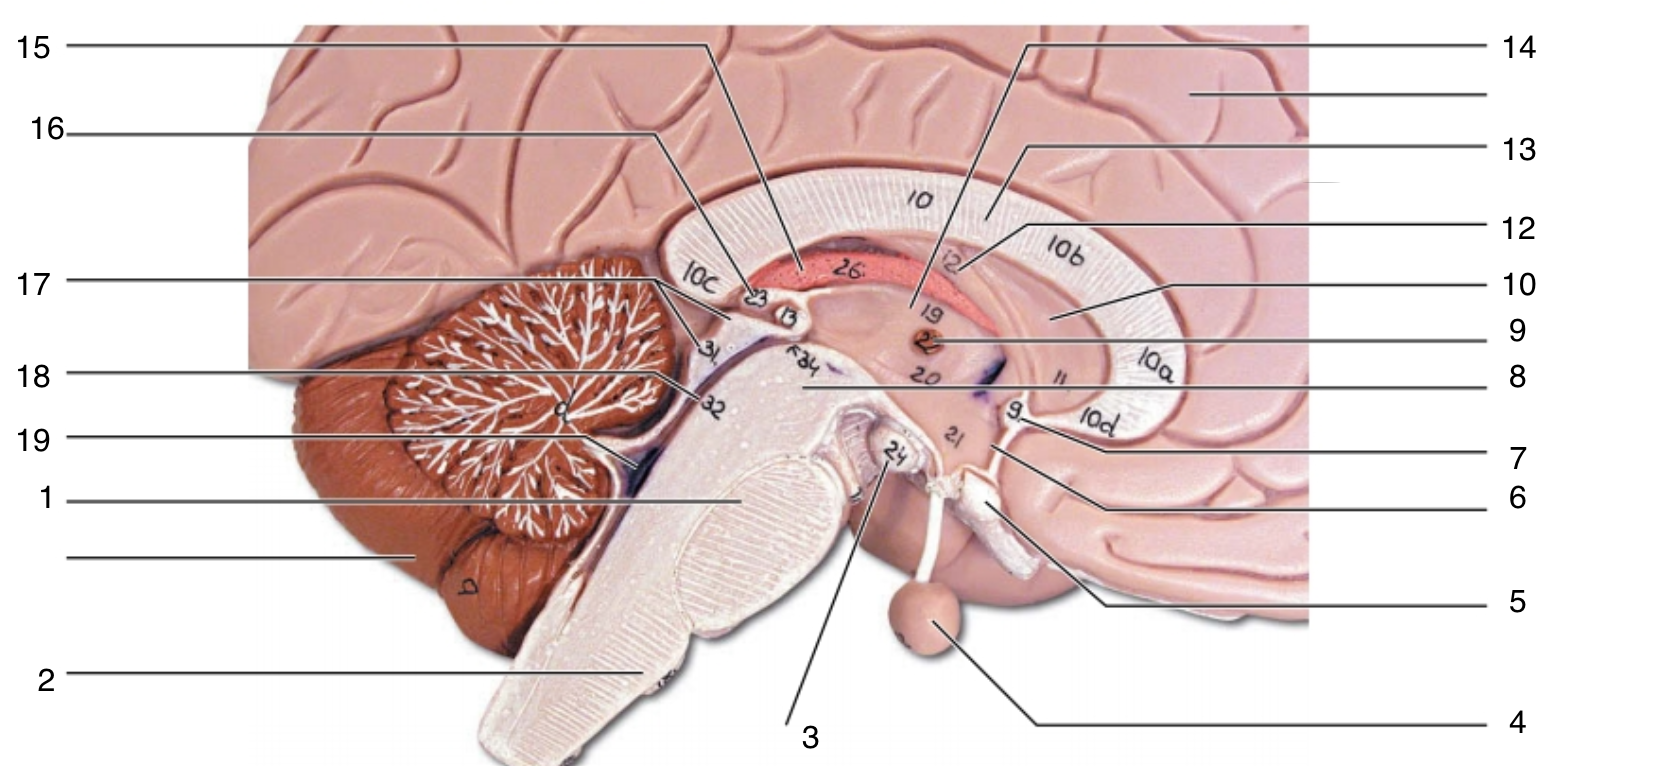

Brain Stem

1

pons

1

2

medulla oblongata

2

3

mammillary body

3

4

pituitary gland

4

5

optic chiasma

5

6

hypothalamus

6

7

anterior commissure

7

8

midbrain

8

9

interthalamic adhesion

9

10

septum pellucidum

10